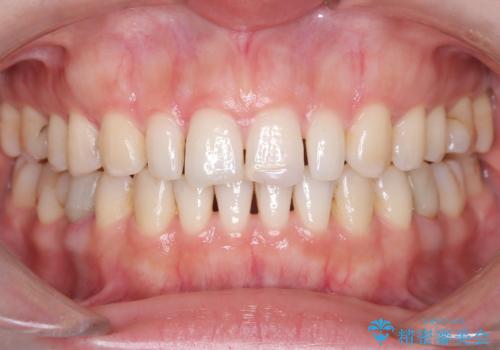

- 歯並びを矯正で整えたあと、上顎左右2番の歯(前歯の横の歯)の「矮小歯(歯が小さい状態)をオールセラミッククラウンで審美修復した症例です。

矯正によって歯並びはきれいに整いましたが、前歯全体のバランスをより自然で美しく仕上げるため、上顎左右2番にオールセラミッククラウンによる審美修復を行いました。

矯正治療後に、「歯の大きさや形が気になる」「前歯の完成度をもう一段階上げたい」という方に適した治療です。